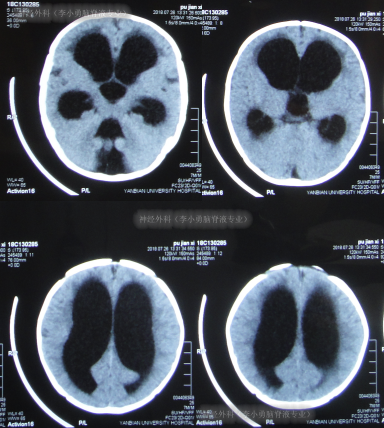

但出院后2天即2018年7月26日,晨起患儿双眼出现对眼,喂奶后再次喷射性呕吐,就诊于第2家医院:吉林省珲春市某医院,检查后认为患儿较重建议转院,于是当天就诊于上级的第3家医院:吉林省延边市某三甲医院,查头颅CT示脑积水(图-1)。

图-1:2018年7月26日头颅CT